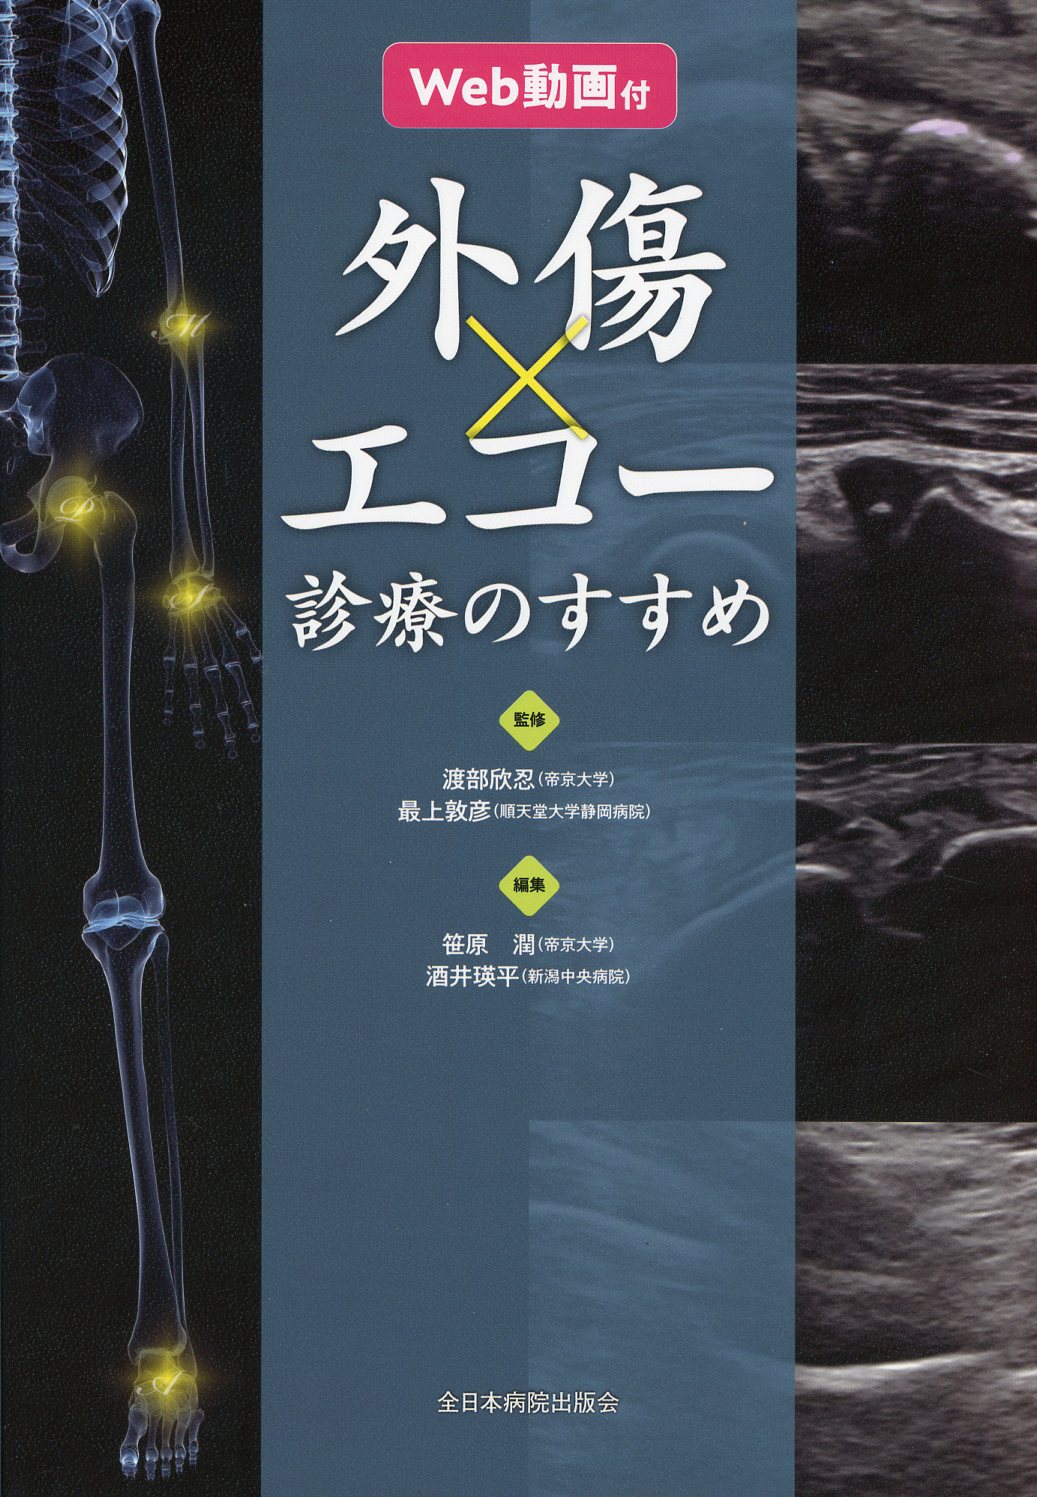

大学生 割引 外傷エコー診療のすすめ【Web動画付】 / 高陽堂書店 健康・医学

大学生 割引 外傷エコー診療のすすめ【Web動画付】 / 高陽堂書店 健康・医学

外傷エコー診療のすすめ【Web動画付】 / 高陽堂書店,

外傷エコー診療のすすめ【Web動画付】 / 高陽堂書店, 外傷エコー診療のすすめ【Web動画付】 | 渡部欣忍, 最上敦彦,

外傷エコー診療のすすめ【Web動画付】 | 渡部欣忍, 最上敦彦, 楽天ブックス: 【Web動画付】外傷エコー診療のすすめ - 渡部 欣,

楽天ブックス: 【Web動画付】外傷エコー診療のすすめ - 渡部 欣, 番外編☆外傷患者の出血源を検索せよ!:日経メディカル「【Web動画付】外傷エコー診療のすすめ」渡部 欣忍 / 最上敦彦 / 笹原潤 / 酒井瑛平定価: ¥ 8000閲覧いただきありがとうございますエコーの勉強に使用していました特に目立った汚れや傷はありませんが見落としている所があるかもしれません神経質な方はご遠慮下さい#渡部欣忍 #渡部_欣忍 #最上敦彦 #笹原潤 #酒井瑛平 #本 #自然/医療・薬学・健康

番外編☆外傷患者の出血源を検索せよ!:日経メディカル「【Web動画付】外傷エコー診療のすすめ」渡部 欣忍 / 最上敦彦 / 笹原潤 / 酒井瑛平定価: ¥ 8000閲覧いただきありがとうございますエコーの勉強に使用していました特に目立った汚れや傷はありませんが見落としている所があるかもしれません神経質な方はご遠慮下さい#渡部欣忍 #渡部_欣忍 #最上敦彦 #笹原潤 #酒井瑛平 #本 #自然/医療・薬学・健康